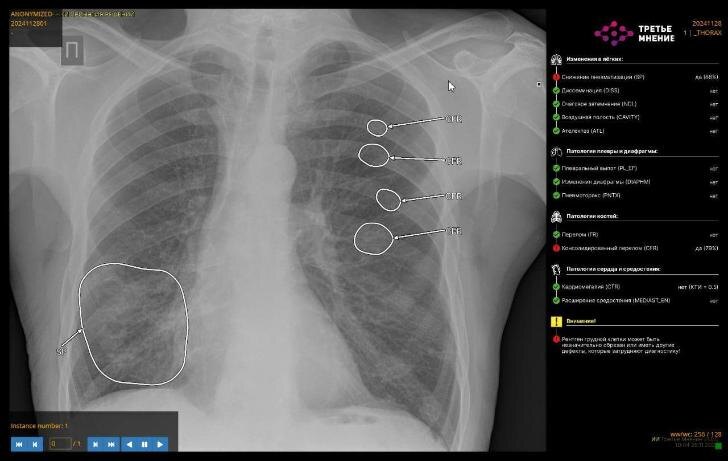

Министр отметил, что развитие комплексных решений на базе ИИ является приоритетным. Сейчас технологии способны выявлять до 14 типов патологий при компьютерной томографии органов грудной клетки. Среди новых возможностей – диагностика пневмоторакса, изменений в подмышечных лимфоузлах, переломов рёбер, а также признаков пневмонии, плеврита, патологий надпочечников и позвоночника.

Кроме того, ИИ активно используется для анализа изменений в лимфатических узлах. При обнаружении проблемной зоны система её подсвечивает, и врач уже сопоставляет информацию с клинической картиной и результатами обследования. Это помогает выявлять заболевания без плана и начинать лечение на более ранних стадиях.